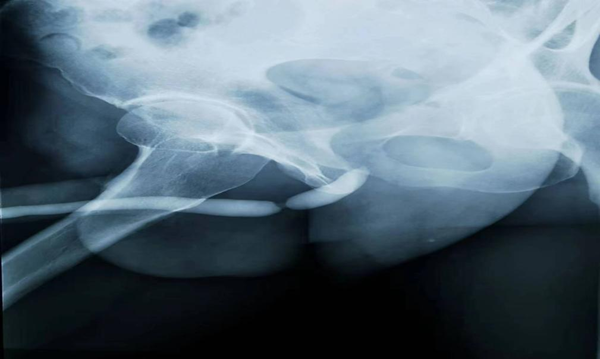

如不是亲眼所见,今年75岁的郑奶奶和家人都万万不敢相信,她身上的膀胱结石竟比苹果还大!近日,湘雅常德医院泌尿外科为75岁患者成功取出这一巨大结石,直径最长达11厘米。湘雅常德医院...